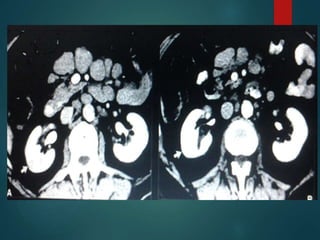

Lymphoma…

• MC cause of lymphadenopathy.

• The CT attenuation at diagnosis is

homogeneous in most cases with minimal to no

enhancement.

• Heterogeneous attenuation …

Aggressive histology

During treatment

• Calcification may occur

Lymphoma… • MC causeof lymphadenopathy. • The CT attenuation at diagnosis is homogeneous in most cases with minimal to no enhancement. • Heterogeneous attenuation … Aggressive histology During treatment • Calcification may occur

• #35 •1. Usually there are other sites with lymphoma. .

• #36 Classic feature is Sandwitch sign…multiple lymphnodes encasing the mesenteric vessels by both side.